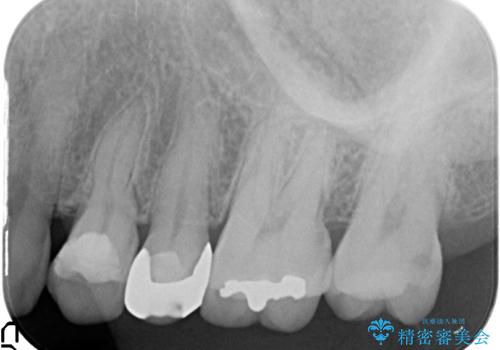

- 左上5番目の歯がしみるといらっしゃった方の症例です。

頬側の樹脂及び銀歯を除去後、オールセラミッククラウンにて補綴を行いました。